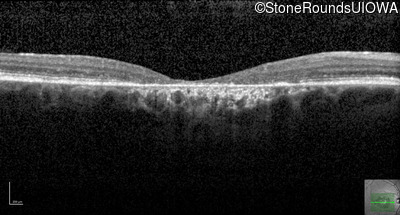

Optical Coherence Tomography - Right - 20/200 -2 sc

Exemplar / OCT Stack